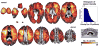

The Wechsler Adult Intelligence Scale (WAIS) assesses a wide range of cognitive abilities and impairments. Factor analyses have documented four underlying indices that jointly comprise intelligence as assessed with the WAIS: verbal comprehension (VCI), perceptual organization (POI), working memory (WMI), and processing speed (PSI). We used nonparametric voxel-based lesion-symptom mapping in 241 patients with focal brain damage to investigate their neural underpinnings. Statistically significant lesion-deficit relationships were found in left inferior frontal cortex for VCI, in left frontal and parietal cortex for WMI, and in right parietal cortex for POI. There was no reliable single localization for PSI. Statistical power maps and cross-validation analyses quantified specificity and sensitivity of the index scores in predicting lesion locations. Our findings provide comprehensive lesion maps of intelligence factors, and make specific recommendations for interpretation and application of the WAIS to the study of intelligence in health and disease.